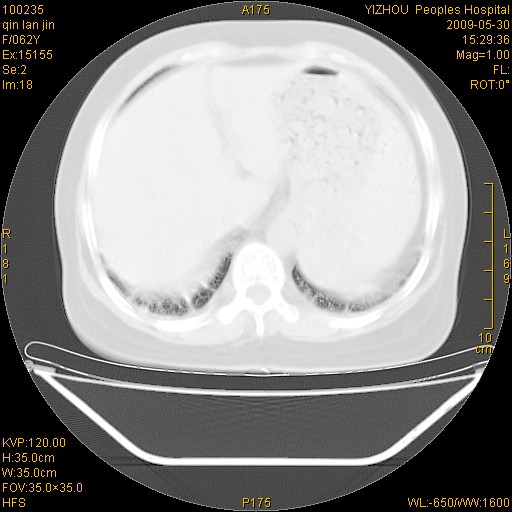

标题: CT20268:肺泡癌?间质性肺炎? [打印本页]

标题: CT20268:肺泡癌?间质性肺炎?

女,62岁,近二年经常咳嗽,近二个月,消瘦、乏力。

前面一张胸片是今天照的,后面一张胸片是去年9月份的。